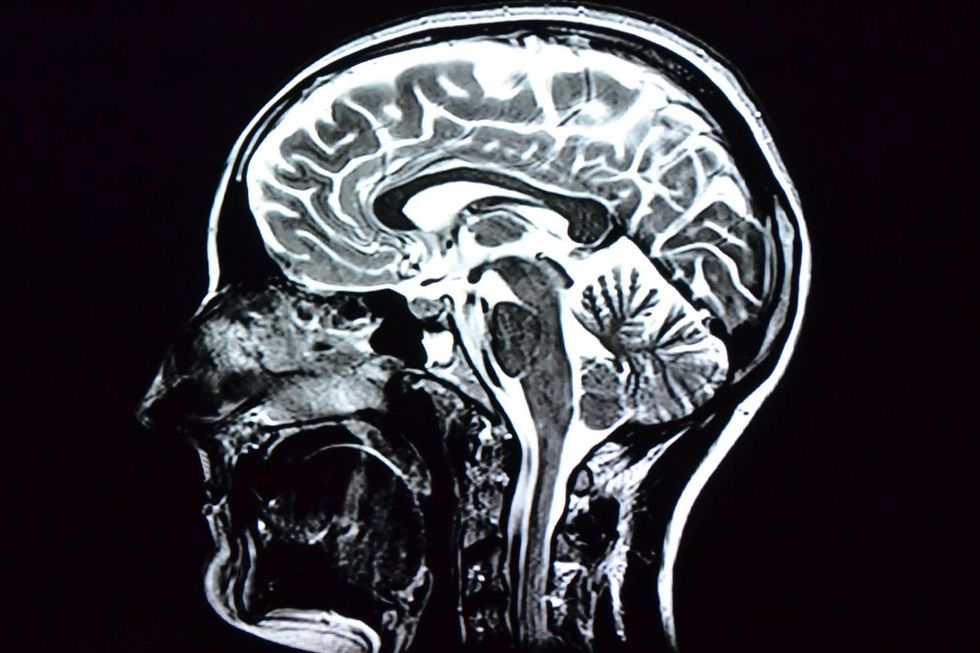

High-quality plant-based diets are linked to a lower chance of Alzheimer's disease and related dementias

|GETTY